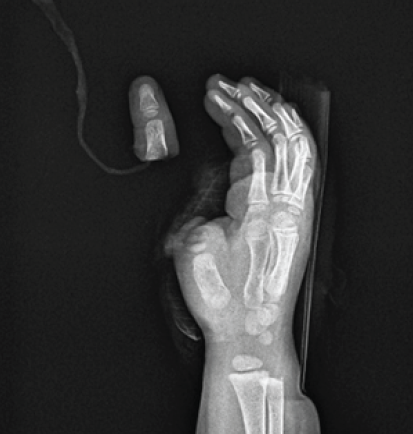

A 2-year-old girl presented to our tertiary care hospital with a complete avulsion amputation of the right thumb at the level of the proximal phalanx following a street dog bite. The incident occurred in the morning. The parents acted swiftly, demonstrating exceptional presence of mind by retrieving the amputated segment from the dog’s mouth within a minute. They immediately transported the child to a primary health center, where the digit was preserved in a moist cloth, sealed in a plastic bag, and placed on ice in accordance with preservation guidelines. Notably, the child had sustained a separate dog bite one week prior, and rabies post-exposure prophylaxis had already been initiated. Her immunization history was current, including tetanus, with no known allergies, previous surgeries, or chronic conditions; growth and development were appropriate for her age. The patient arrived at our facility approximately three hours post-injury, alert and hemodynamically stable. Local examination revealed a Gustilo–Anderson Type IIIC injury with a transverse fracture at the base of the proximal phalanx and complete avulsion, classified as Tamai Zone III (Fig. 1).

Figure 1: At arrival.

The wound edges displayed irregular tearing consistent with a bite mechanism. However, the amputated unit was well-preserved, with clearly identifiable tendons, arteries, and nerves. X-rays confirmed the amputation level and absence of foreign bodies or major contamination, validating the efficacy of initial management (Fig. 2).

Figure 2: Pre-operative X-ray.